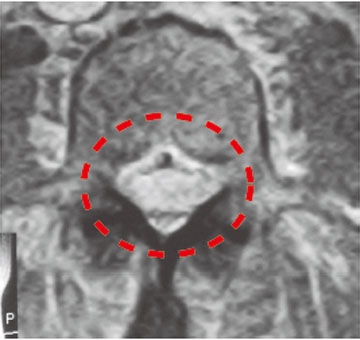

脊柱狭窄症患者伴有强度的间歇性跛行的MRI造影明显可见神经被压迫面)

MRI影像可见,两侧神经被关节突起压迫,因此会引发神经痛,步行障碍。